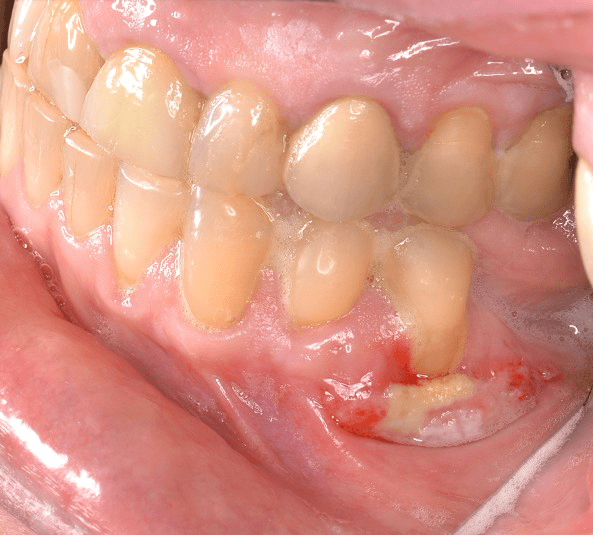

Complication Bone Graft is Exposed Platelet PRF Treatment Dental Gum Graft Complications Complications are rare, and insurance may or may not. The recovery period is typically a few weeks and usually involves eating soft or cold foods to avoid damaging the graft. But see your doctor right away if you notice any oozing or unexpected bleeding around the graft site. What are the risks or complications of gum graft surgery? A poorly. Dental Gum Graft Complications.